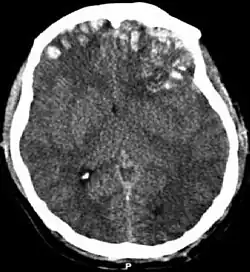

Hematomas, also focal lesions, are collections of blood in or around the brain that can result from hemorrhage.[11] Intracerebral hemorrhage, with bleeding in the brain tissue itself, is an intra-axial lesion. Extra-axial lesions include epidural hematoma, subdural hematoma, subarachnoid hemorrhage, and intraventricular hemorrhage.[38] Epidural hematoma involves bleeding into the area between the skull and the dura mater, the outermost of the three membranes surrounding the brain.[11] In subdural hematoma, bleeding occurs between the dura and the arachnoid mater.[23] Subarachnoid hemorrhage involves bleeding into the space between the arachnoid membrane and the pia mater.[23] Intraventricular hemorrhage occurs when there is bleeding in the ventricles.[38]